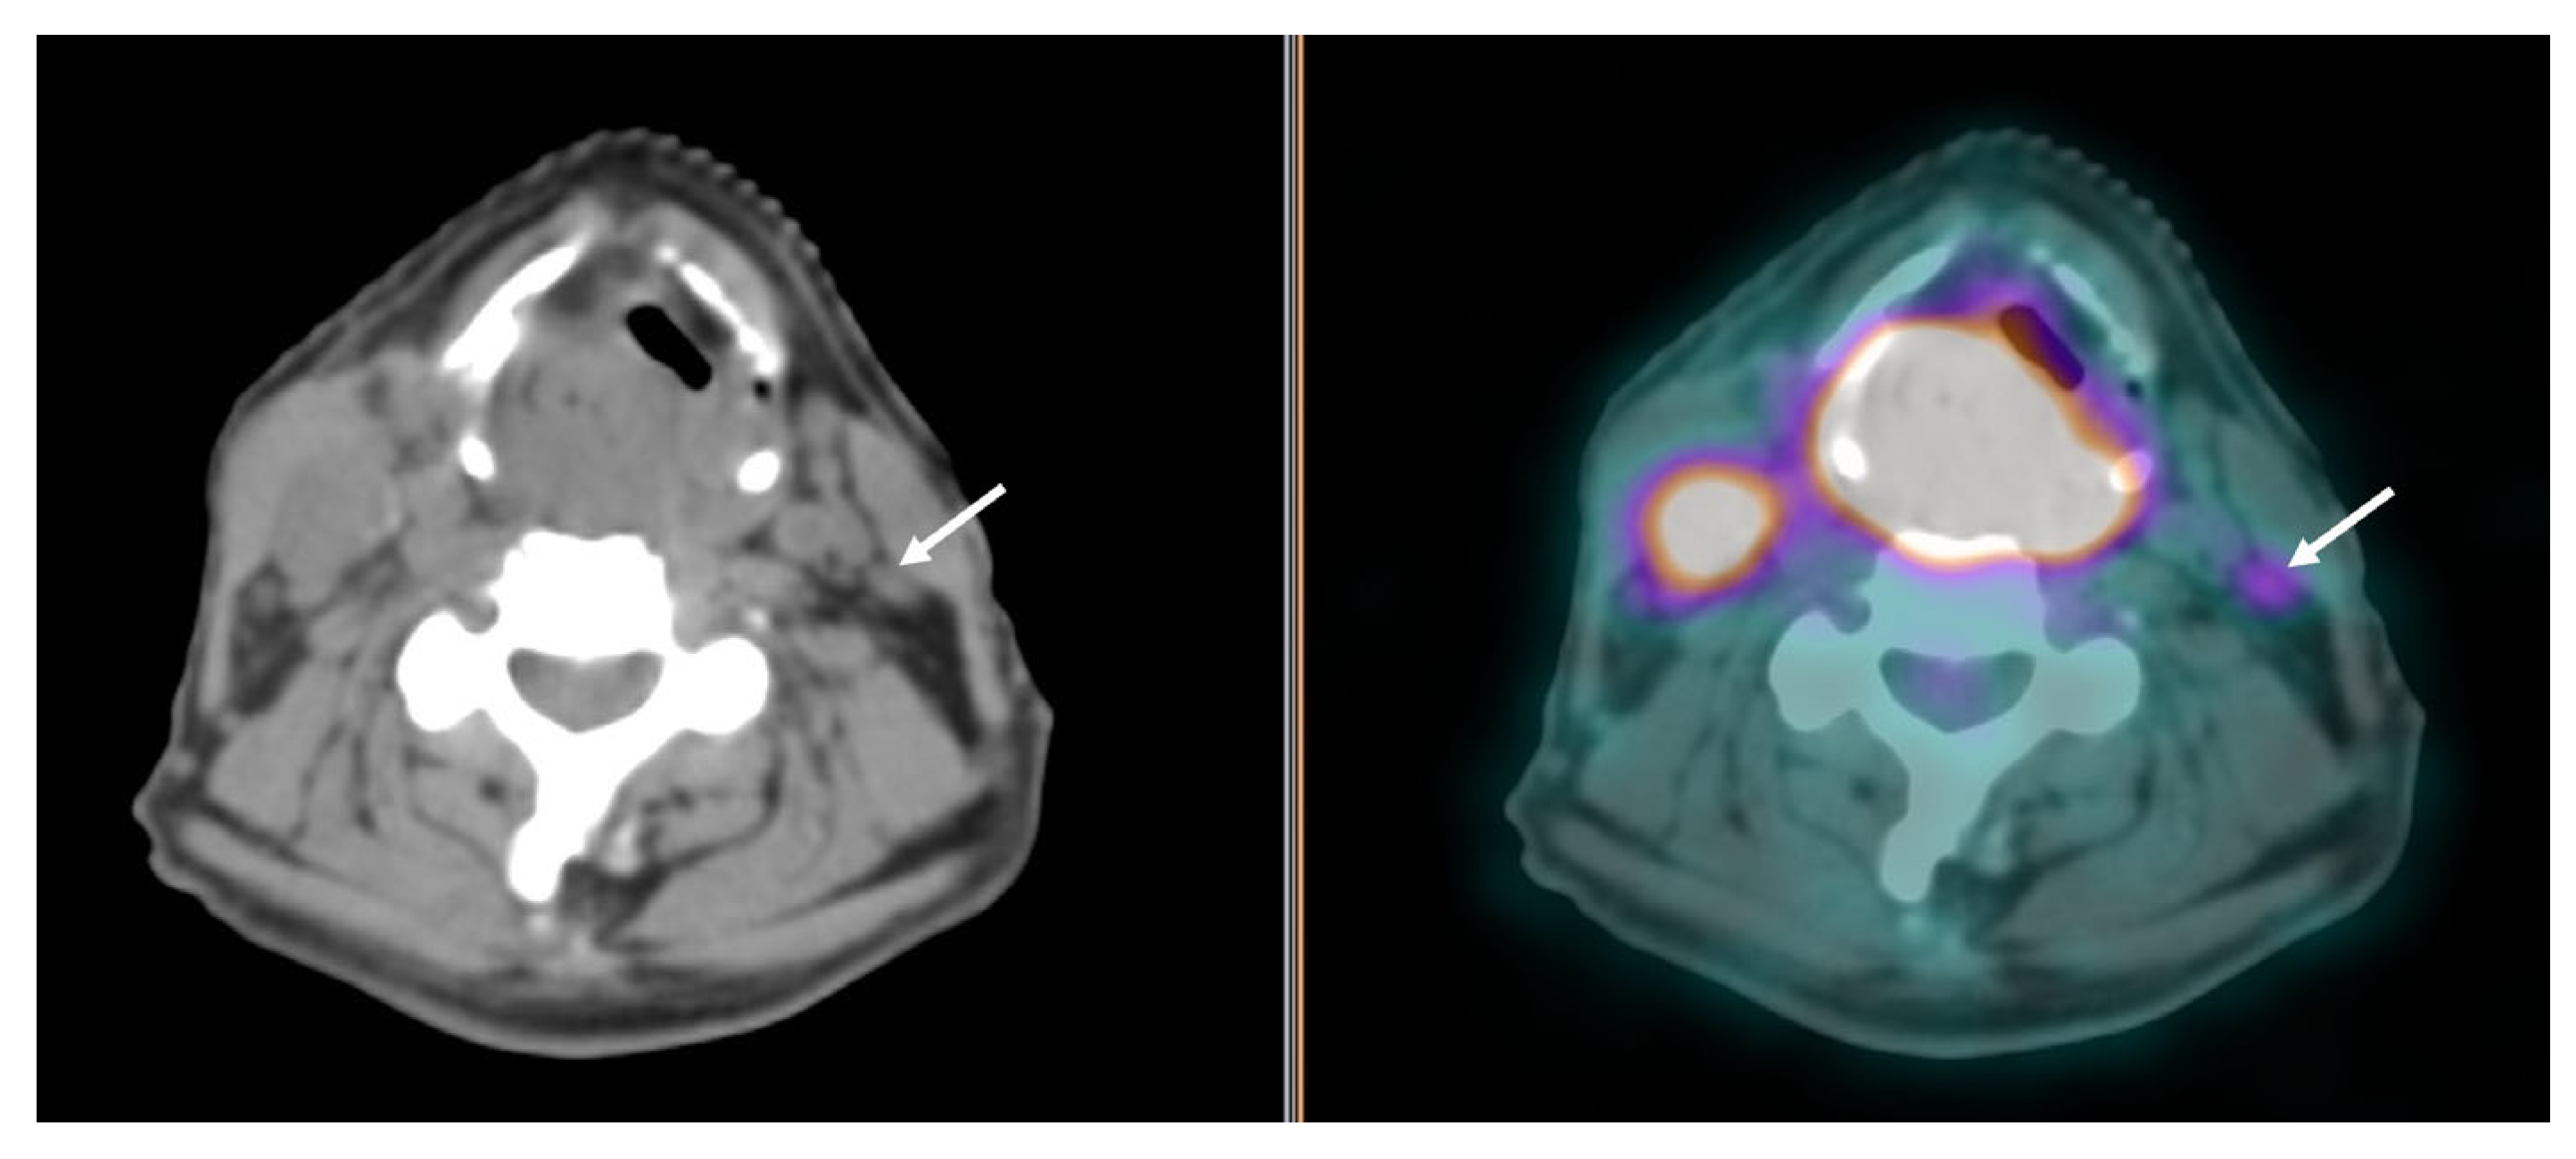

3.2. Cervical Lymph Node Assessment

- Haerle, S.K.; Strobel, K.; Ahmad, N.; Soltermann, A.; Schmid, D.T.; Stoeckli, S.J. Contrast-enhanced 18F-FDG-PET/CT for the assessment of necrotic lymph node metastases. Head Neck 2011, 33, 324–329. [Google Scholar] [CrossRef] [PubMed]

- Roh, J.L.; Park, J.P.; Kim, J.S.; Lee, J.H.; Cho, K.J.; Choi, S.H.; Nam, S.Y.; Kim, S.Y. 18F fluorodeoxyglucose PET/CT in head and neck squamous cell carcinoma with negative neck palpation findings: A prospective study. Radiology 2014, 271, 153–161. [Google Scholar] [CrossRef] [PubMed]